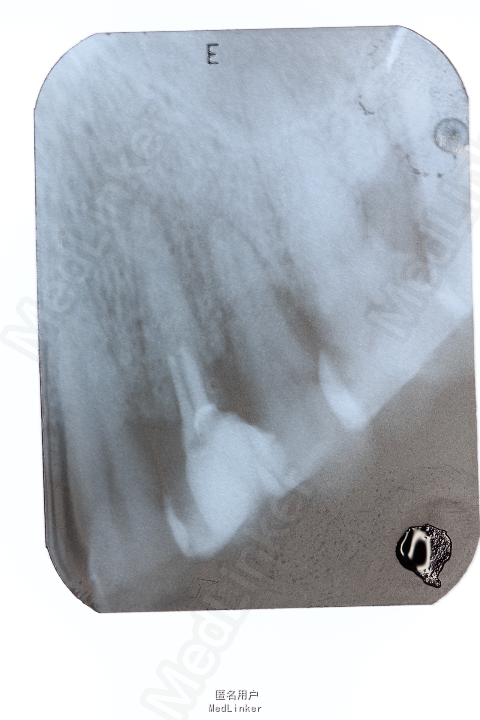

患者男,3日前于外院行根管治疗过程中遇器械分离,要求取出。

扩大根管上段通道,利用P5+ET25+橡皮樟,在显微镜直视下,从器械断端的颊舌向分别去除牙本质,解除器械卡死,取出分离器械。

一周后复诊,患者自述患牙无明显不适。患者不愿继续进行根管治疗,担心接下来的治疗过程中再次发生器械分离的风险,经劝说无效,上端改用玻璃离子充填。 在日常的根管预备过程中,器械分离事件难免会发生,应该做到尽量避免,沉着应对,冷静解决。但要明确器械分离取出的必要性,安全性。做好与患者的术前术后沟通。